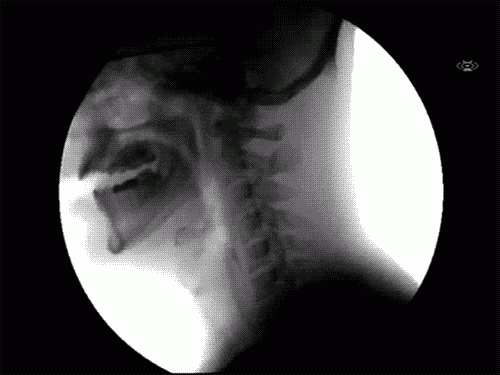

8. Ketika menelan.